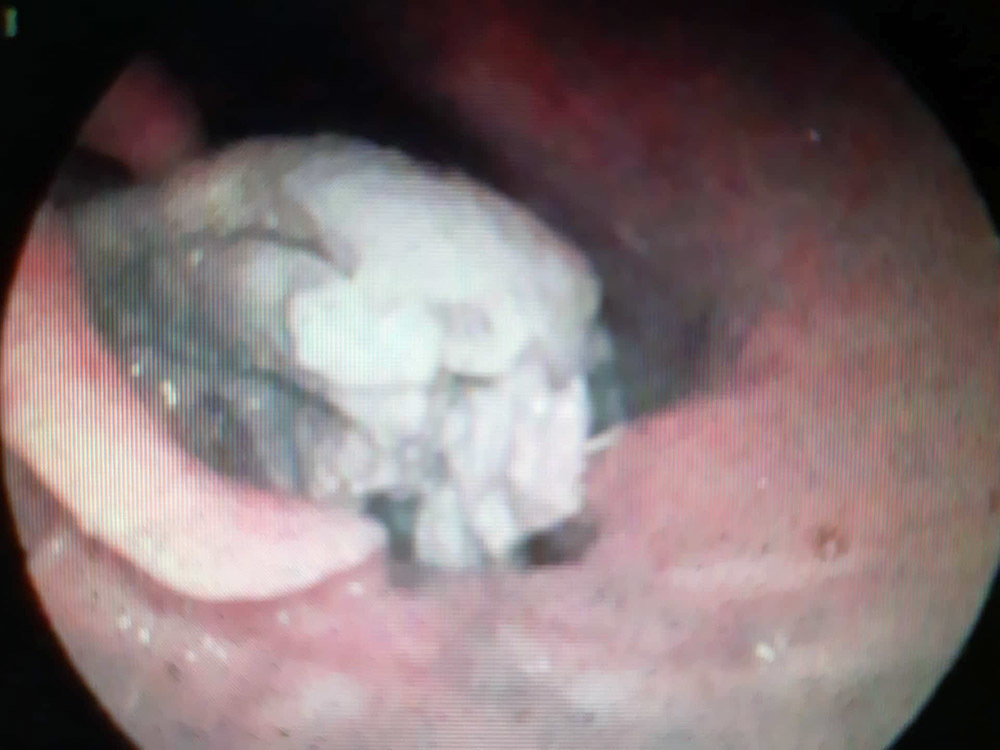

Hình ảnh phao câu vịt xiêm nằm ở hố lê hai bên chèn ép thanh quản của bệnh nhân M.

Sau khi thăm khám, bác sĩ đã chỉ định nội soi họng và phát hiện dị vật nằm ở hố lê hai bên chèn ép thanh quản.

Bác sỹ đã xử trí gắp dị vật ra là một cái phao câu vịt tróc da còn nguyên thịt và xương, kích thước 3cm x 3,5cm x 5cm, nằm kẹt cứng ngang hố lê hai bên, chèn ép gần hết thanh quản.

Bác sĩ Lưu cho biết: "Đây là một trường hợp đặc biệt bởi miếng phao câu vịt khá lớn đã nằm kẹt cứng vào hố lê hai bên, chèn ép thanh quản và gây khó khăn khi thực hiện thủ thuật. Chúng tôi phải xử lý cẩn thận để không làm tổn thương thực quản. Sau hơn 20 phút chúng tôi đã gắp dị vật ra khỏi thực quản bệnh nhân”.